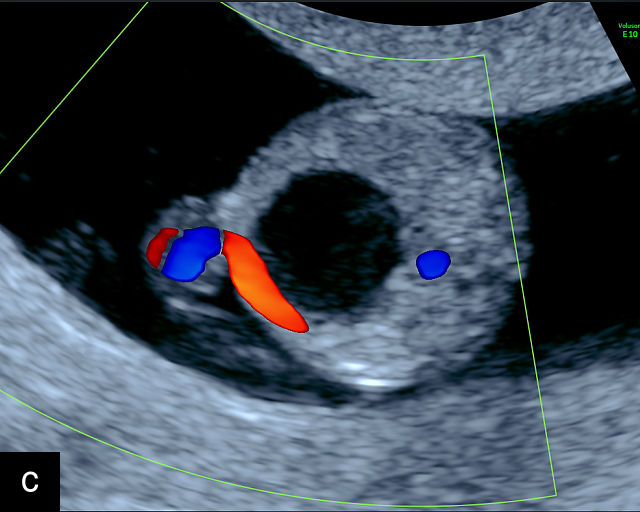

The umbilical cord serves as the lifeline connecting the fetus to the placenta. It arises from the midportion of the fetal abdomen and typically inserts into the center of the placenta (Figure 16). The average length of the umbilical cord is approximately 55 cm (22 inches).185 It contains three vessels: two arteries, which originate from the fetal left and right internal iliac arteries, and one vein, collectively referred to as a three-vessel cord.

16

Normal appearance of the umbilical cord with two umbilical arteries and a single vein. (a–c) Cross-section of the umbilical cord on grayscale (a,b) and power Doppler (c) ultrasound. In the normal cord, three vessels are visible: a larger umbilical vein and two smaller umbilical arteries. This characteristic appearance is often referred to as the 'Mickey Mouse' sign, the larger circle (umbilical vein) representing Mickey’s face while the smaller circles (arteries) form his ears. (d–g) Grayscale (d) and color Doppler (e–g) images of transverse section of the lower fetal abdomen showing the two umbilical arteries diverging around the fetal bladder. (h) Longitudinal ultrasound view with color Doppler of a normal umbilical cord showing three vessels present in each coil: two arteries with flow in one direction and a single vein with flow in the opposite direction.

The umbilical vein carries oxygenated blood from the placenta to the fetus, while the two umbilical arteries return deoxygenated blood and waste products from the fetus to the placenta for exchange with the maternal circulation. These vessels are surrounded and protected by Wharton’s jelly, a specialized connective tissue derived from the extraembryonic mesoblast, which cushions the vessels and prevents compression. As the umbilical cord approaches its placental insertion, the two arteries form Hyrtl’s anastomosis, a connection that helps equalize blood flow between the arteries.

At a minimum, the mid-trimester ultrasound should include identification and documentation of the umbilical cord's fetal and placental insertions, as well as the number of cord vessels.66,186,187 In a transverse grayscale section of the cord, the two umbilical arteries can be visualized alongside the larger, thinner-walled umbilical vein, creating a characteristic ‘Mickey Mouse’ appearance (Figure 16a–c). Additionally, in a transverse section of the lower fetal abdomen, the umbilical arteries are seen encircling the fetal bladder. This can be seen on grayscale ultrasound and confirmed with color flow Doppler (Figure 16d–g).